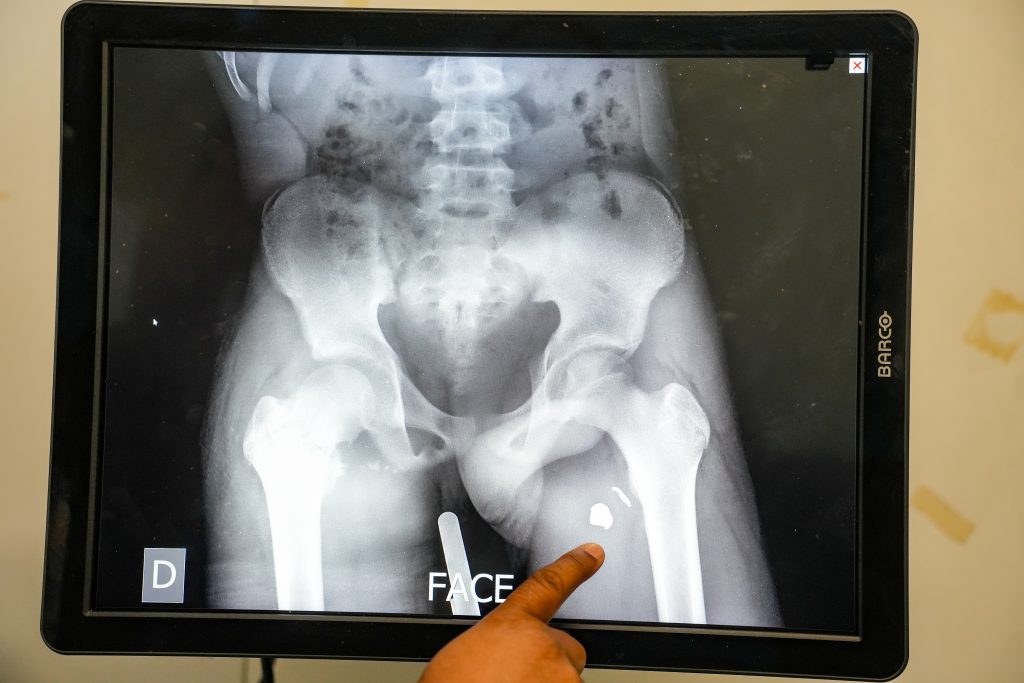

Patients requiring surgical care are referred to Tabarre trauma hospital, one of the last facilities in the capital still able to provide free specialized surgical care. These referrals, however, occur under precarious conditions. For over a year, MSF has had to suspend our ambulance service due to repeated threats and attacks on vehicles and patients during transfers between medical facilities. Some vehicles from the state ambulance center remain operational, but their capacity is insufficient. As a result, many critically injured patients arrive late, after fighting has subsided in their neighbourhoods, often transported by non-medical means such as mototaxis.

In 2025, 686 patients injured by violence were admitted to MSF’s Tabarre hospital, nearly 90 per cent of them with gunshot wounds. Among those shot were 193 women and 47 children under 14. The trend shows no sign of slowing: on Jan. 6, 2026, alone, MSF admitted eight patients with gunshot wounds in a single day, highlighting the persistence and intensity of violence in the capital.